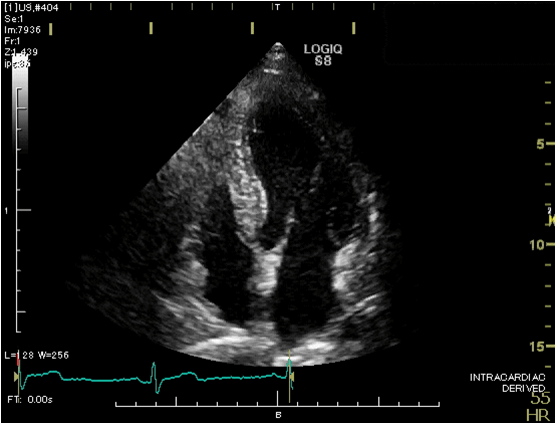

心臓超音波検査

(心エコー検査)

心臓の形や動き、弁の状態、血液の流れなどを調べる検査です。

ベッドに左向きで横になっていただき、胸にゼリーを塗り心臓を観察します。

必要に応じて仰向けや右向きになったり息を止めたりして撮影します。

検査時間は通常20~30分程度です。

検査着に着替えていただき、検査を行っています。普段の服装でも検査はできますが、ゼリーが付着する可能性があるため、検査着への着替えにご協力ください。

超音波診断装置(心臓用)

心臓の超音波画像